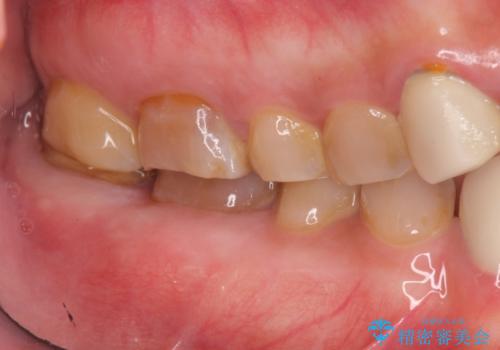

手術を行い歯ぐきの位置が改善することで歯がしみる症状が大幅に改善されたと満足いただくことができました。